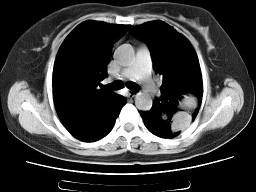

问题 女,52岁,左侧背痛一月,胸部CT如图,最可能的诊断为 ( )

选项 A、左肺炎性假瘤 B、肺隔离征 C、左肺周围型肺癌 D、左肺感染 E、左肺中央型肺癌

答案 A